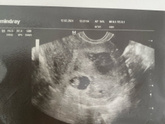

Была сегодня на узи. Все растет и развивается :) отслойка становится тоньше, малыш растет. Все слава Богу!

Врач повернула мне экран на котором были видны ножки и что то между ними ??? но ничего не сказала :) не знаю, можно ли это считать определением … Читать далее

27 иду на узи повторное — очень надеюсь, что отслойка стала меньше и не угроза прошла.

29 иду в ЖК к гинекологу. По результатам узи должны уже поставить на учет и дать направление на скрининг.